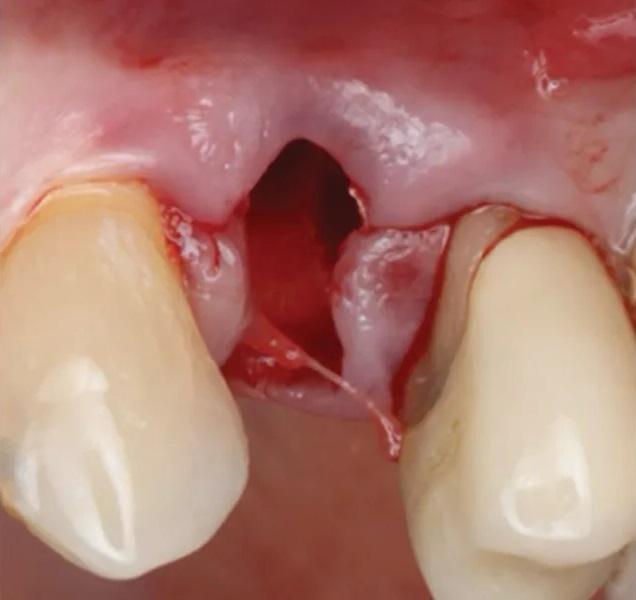

Существующая реставрация (№ 2.4) была разделена для получения доступа к фуркации. Оба корня (щечный и небный) были удалены с использованием периотомов, элеваторов и щипцов. Лунка была очищена от грануляционной ткани, которая отправлена на гистопатологический анализ. ПА рентгеновский снимок подтвердил полное удаление корней. Процедура САГ была выполнена с использованием упомянутого выше резорбируемого ксеногенно-аллопластического биоматериала (OsteoGen Plug), который был адаптирован в лунку (Фото 6). ПА рентгеновский снимок подтвердил правильное размещение биоматериала. Участок был ушит швом из политетрафторэтилена (ПТФЭ) (Фото 7 – Фото 10). Пациенту были даны инструкции по гигиене полости рта и послеоперационному уходу.

Фото 7. Удаление первого премоляра верхней челюсти слева. Свежая лунка демонстрирует сохраненный контур мягких тканей.